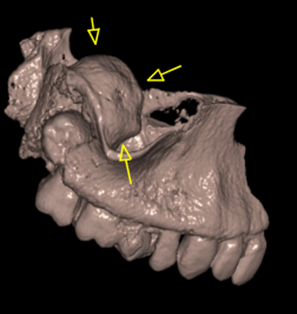

Περίπτωση εκτεταμένης οδοντοφόρου κύστης σχετιζόμενης με τον έγκλειστο 3ο γομφίο 18 όπου παρατηρείται εμπλοκή του δεξιού ιγμορείου άντρου σε γυναίκα ασθενή ηλικίας 45 ετών.

Η κύστη έχει προκαλέσει ιδιαίτερα εκτεταμένη υπέγερση του εδάφους του ιγμορείου άντρου προβάλλοντας εντός αυτού και καταλαμβάνοντας μεγάλο τμήμα της αεροφόρου του κοιλότητας.

Παρατηρείται επίσης λέπτυνση και ήπια έκπτυξη του πλαγίου τοιχώματος του ιγμορείου άντρου.